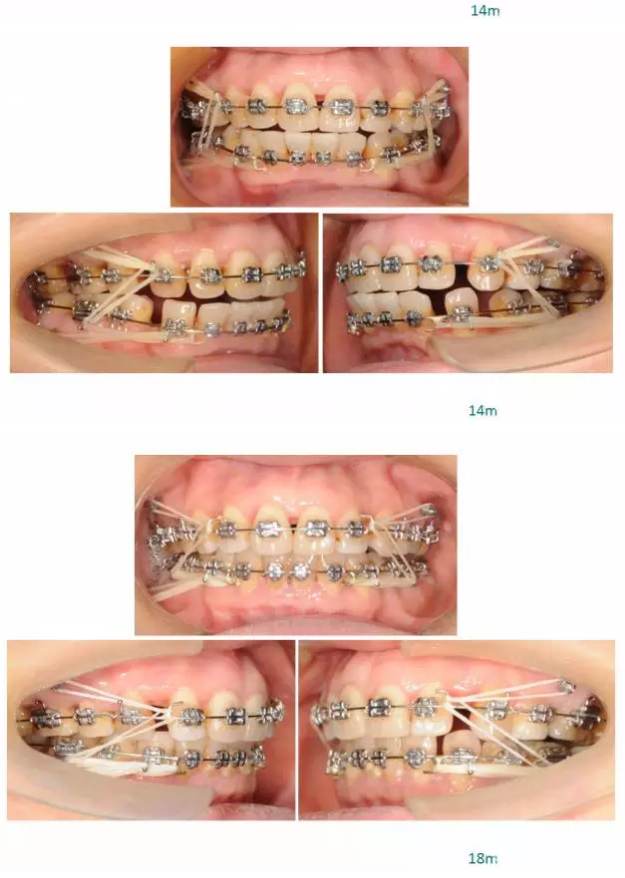

【原創(chuàng)博客】這樣的代償矯治大家滿意嗎?(重度骨性二類)——侯志明

QQ圖片20150824150628.png

QQ圖片20150824150643.png